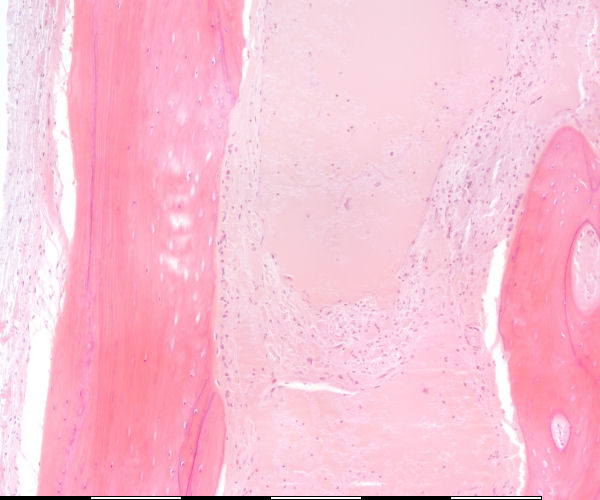

Osteosiete / Osteocytes

Lakunae / Lacunae

Groeilyne / Growth reversal lines

Aktiewe periosteum / Active periosteum

Losmasige bindweefsel / Loose connective tissue

Osteoblaste / Osteoblasts

Laag van osteoblaste / Layer of osteoblasts

Lamellêre laag kortikale been / Lamellar layer of cortical bone